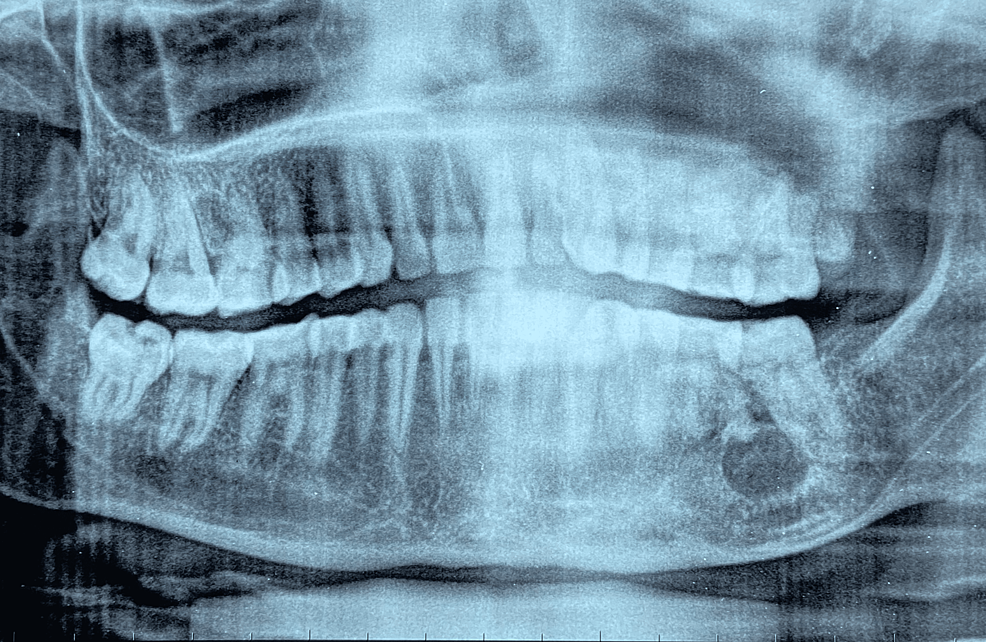

Maxillary Odontogenic Keratocyst . — the odontogenic keratocyst (okc) is one of the most aggressive odontogenic cysts. odontogenic keratocysts (okc), previously known as keratocystic odontogenic tumors (kcot or kot), are rare benign cystic lesions involving the mandible or. The main difference between okcs and other jaw cysts. — an odontogenic keratocyst (okc) is a benign but aggressive intraosseous tumor derived from the. — odontogenic keratocysts (okcs), first described by philipsen in 1956 [1], are benign intraosseous lesions of. figure 5 odontogenic keratocyst between roots of right maxillary incisors (circled by white dots). — odontogenic keratocysts (okc), previously known as keratocystic odontogenic tumours (kcot or kot), are. — the odontogenic keratocyst (okc) is one of the most aggressive odontogenic cysts.

— odontogenic keratocysts (okcs), first described by philipsen in 1956 [1], are benign intraosseous lesions of. figure 5 odontogenic keratocyst between roots of right maxillary incisors (circled by white dots). The main difference between okcs and other jaw cysts. — an odontogenic keratocyst (okc) is a benign but aggressive intraosseous tumor derived from the. odontogenic keratocysts (okc), previously known as keratocystic odontogenic tumors (kcot or kot), are rare benign cystic lesions involving the mandible or. — the odontogenic keratocyst (okc) is one of the most aggressive odontogenic cysts. — odontogenic keratocysts (okc), previously known as keratocystic odontogenic tumours (kcot or kot), are. — the odontogenic keratocyst (okc) is one of the most aggressive odontogenic cysts.

Maxillary Odontogenic Keratocyst The main difference between okcs and other jaw cysts. — an odontogenic keratocyst (okc) is a benign but aggressive intraosseous tumor derived from the. The main difference between okcs and other jaw cysts. — odontogenic keratocysts (okc), previously known as keratocystic odontogenic tumours (kcot or kot), are. — the odontogenic keratocyst (okc) is one of the most aggressive odontogenic cysts. — the odontogenic keratocyst (okc) is one of the most aggressive odontogenic cysts. — odontogenic keratocysts (okcs), first described by philipsen in 1956 [1], are benign intraosseous lesions of. odontogenic keratocysts (okc), previously known as keratocystic odontogenic tumors (kcot or kot), are rare benign cystic lesions involving the mandible or. figure 5 odontogenic keratocyst between roots of right maxillary incisors (circled by white dots).